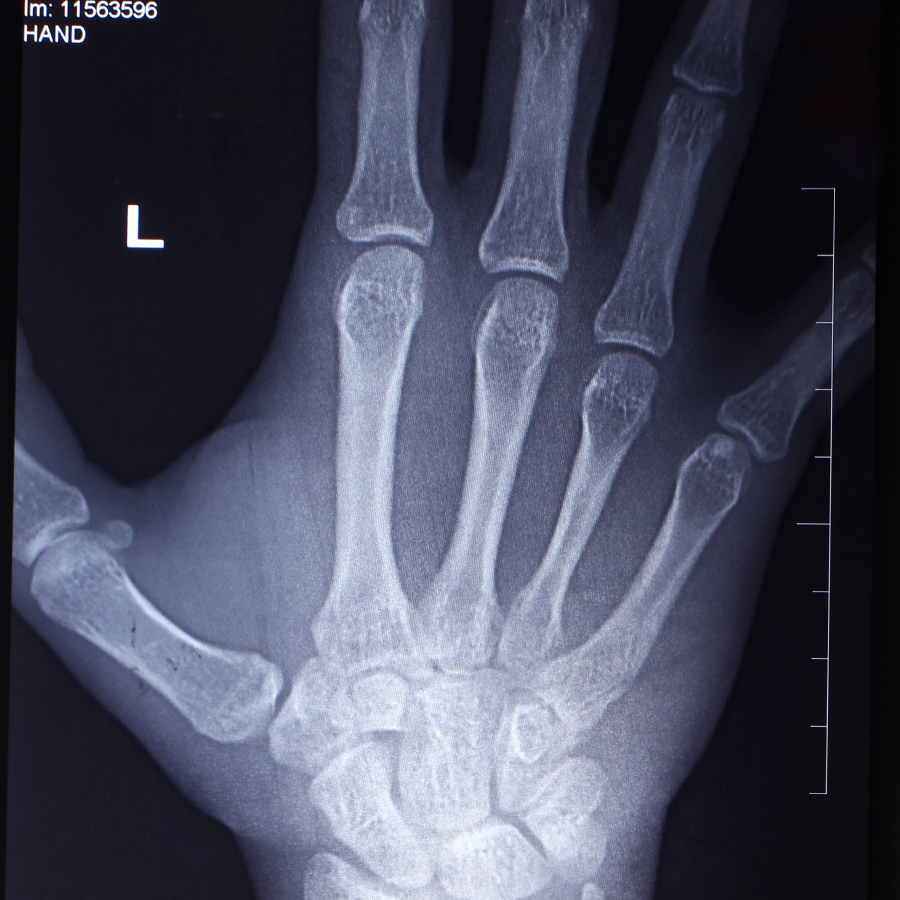

Mano